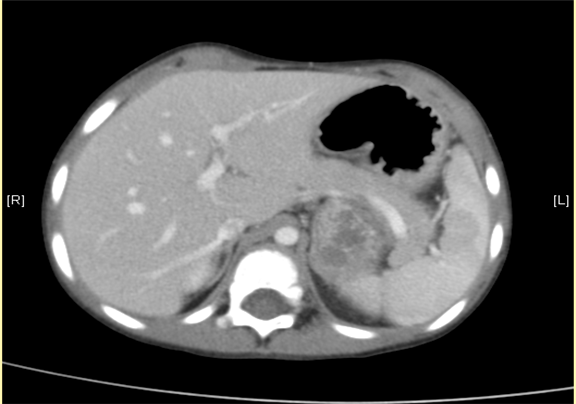

下腹部增强CT示:神经母细胞瘤。

术前CT检查:

静脉期